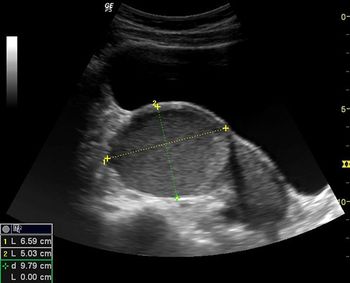

QUIZ: These images are from a young woman with pelvic pain. What do you see?